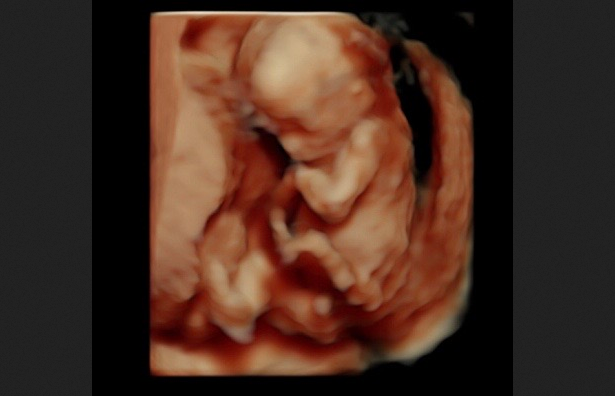

“Miracles Do Happen!” Premature Baby Born at 23 Weeks is Now Home November 11, 2025